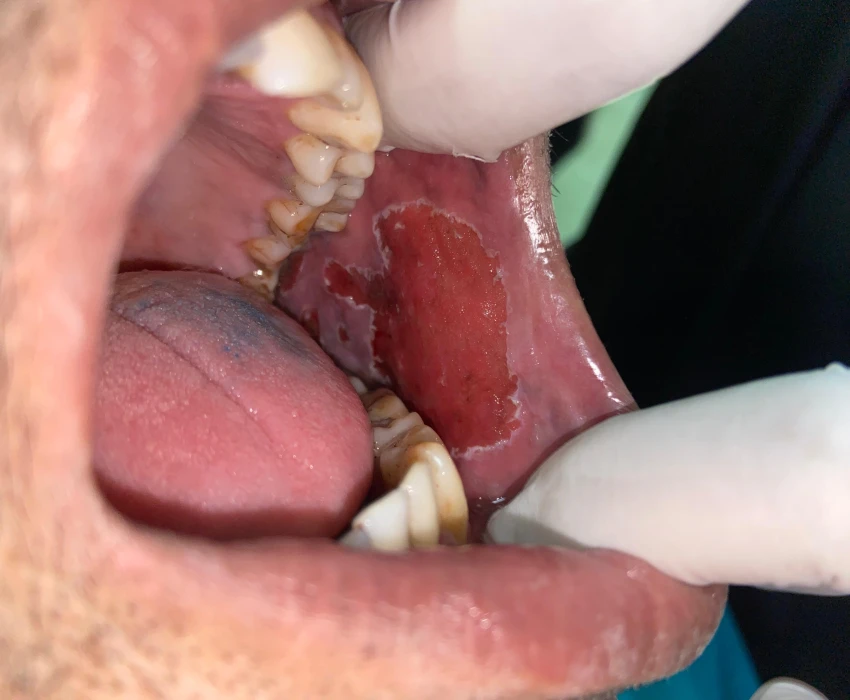

Patient came to the department of Oral medicine and Radiology with a chief complaint of a white patch on the left buccal mucosa.

Intraoral examination- A greysih white keratotic patche with cracked mud appearance was present on the left buccal mucosa. It was extending from second molar to left retrocommisural area and was approximately of 20mm×25mm.

Palpation- It was non- scrappable.

Provisional diagnosis of homogeneous leukoplakia was made.